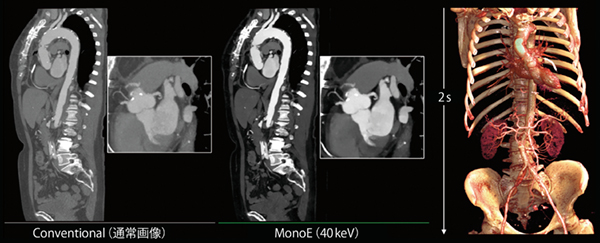

特に,呼吸器疾患の症例では,撮影時間の延長が患者負担の増加や画像品質の低下につながるが,Spectral CT 7500の高速撮影により胸部の撮影時間はわずか1秒で終了し,息止め時間を短縮した検査が提供できる(図2 a)。また,胸腹部・骨盤部検査のような広範囲の検査でも,わずか2秒で検査を完遂することが可能となる(図2 b)。救急搬送された患者や緊急時の検査に対して病変を検索する目的で広範囲撮影が求められる場合にも,Spectral CT 7500の高速撮影により,患者の体動や息止め不良によるモーションアーチファクトを低減できる。

図2 ワイドカバレッジによる高速撮影

a:胸部撮影,scan time:1s

b:胸腹部・骨盤部撮影,scan time:2s

仮想単色X線画像(MonoE)は単一エネルギーで得られる画像を仮想的に表現した画像である。従来のdual energy CTでは,仮想単色X線画像におけるkeV(エネルギー)の違いによるノイズ増加が課題であったが,フィリップスのSpectral CTでは,40〜200keVまで一定のノイズレベルで1keVごとに連続的に表現可能である。これにより,造影効果の増強(CT値の向上)を目的とした低keV画像,金属や骨からのビームハードニングの影響を抑える高keV画像での画質が向上する。造影効果の増強を目的とした低keV画像の使用により,従来では造影剤が使用できない,期待どおりの造影効果が得られないような高齢で腎機能障害のある患者であっても,非常に少ない造影剤使用量で撮影可能となった2),3)(図5)。

図5 低keV画像による造影効果の増強